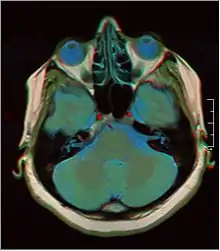

Normal axial T2-weighted MR image of the brain